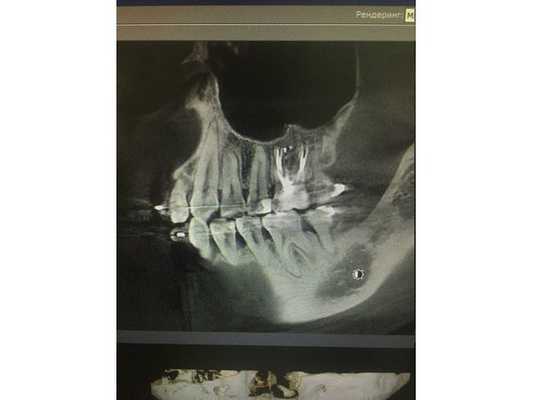

По данным компьютерной томограммы, в зубе три канала, тень пломбировочного материала определяется на всём протяжении каналов в виде непрерывной линейной структуры, рентгенологически верхушки корней зуба обтурированы, т. е. закрыты.

Обнаружен дополнительный канал со стороны щеки, содержимое канала не просматривается. В области нёбного канала видна тень металлической плотности, по конфигурации она соответствует анкерному штифту.

В области верхушек корней визуально определяется деструкция (разрушение) кости без чётких контуров. Плотность участка разрушения снижена, характерный костный рисунок частично сохранён. Область разрушения частично затрагивает альвеолярную бухту гайморовой пазухи. Кортикальная пластинка, отделяющая гайморову пазуху от зубов, в проекции деструкции прослеживается фрагментарно.